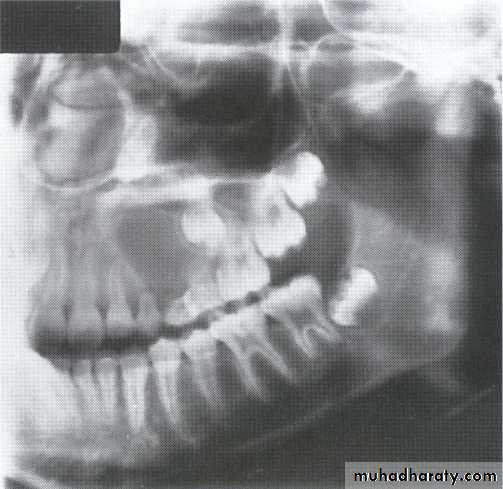

A 11-year-old female with swelling on the right side.

impacted canine